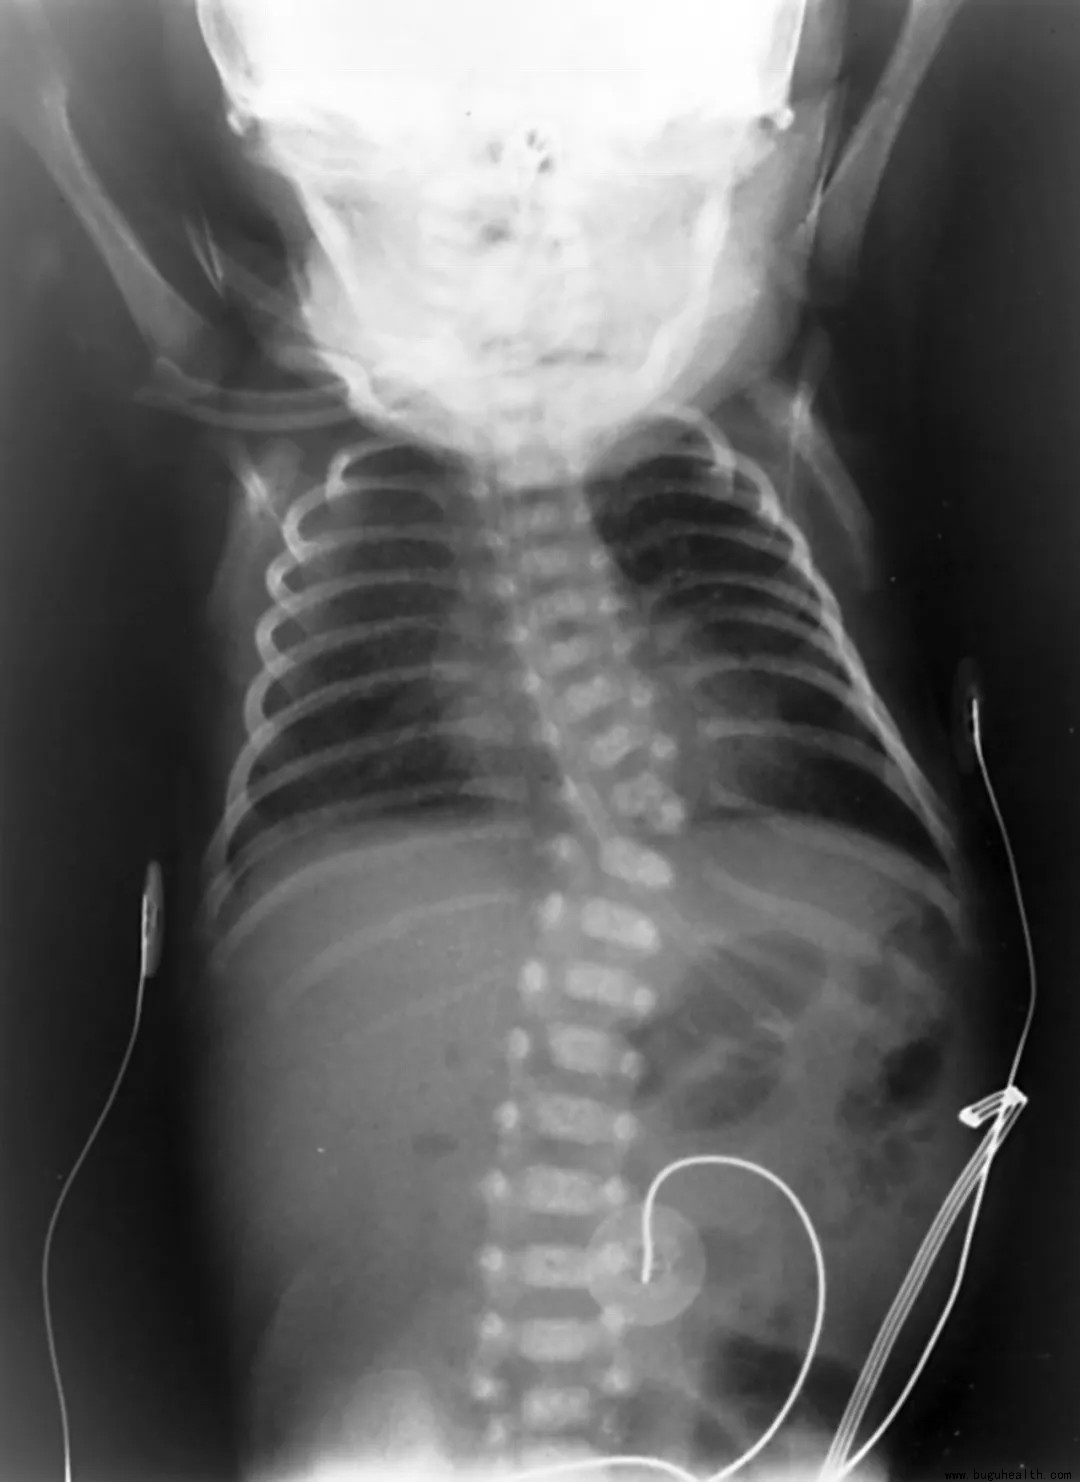

而「先天性脊柱侧弯」是婴儿出生时脊柱的侧弯,在三种主要脊柱侧弯类型中,先天性脊柱侧弯是最不常见的,约万分之一的新生儿受影响。

先天性脊柱侧弯发生在婴儿出生前,椎骨还没有正常形成时。这种类型的脊柱侧弯的严重程度从轻微到危及生命不等。由于脊柱和其他器官系统在怀孕前几周同时形成,因此,许多先天性脊柱侧弯的儿童也有膀胱、肾脏或神经系统问题。

虽然先天性脊柱侧弯在出生时就存在,但它可能并不明显,通常会随着孩子的成长而恶化。

先天性脊柱侧弯发生在怀孕早期,脊柱中的一个或多个椎骨还没有完全形成时,这可能会导致脊柱形成一个被称为「半椎体」的锐角。在其他婴儿中,正在发育的脊椎并没有完全分离成不同的椎骨。

因此,两个或更多的椎骨可能会部分融合,对于一些先天性脊柱侧弯的儿童,脊柱畸形是由这些问题的综合因素引起的。